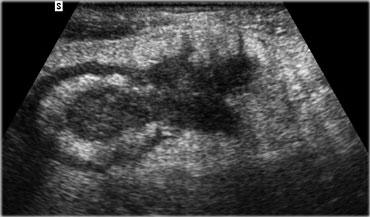

Các trường hợp nên phẫu thuật ngay lập tức

Cuối cùng, có một số bệnh nhân áp xe ruột thừa nên được phẫu thuật ngay lập tức: điều này áp dụng chung cho trẻ em và những bệnh nhân có viêm phúc mạc nặng, cho thấy quá trình bao bọc ngăn chặn đang thất bại.

Phẫu thuật ngay cũng được chỉ định cho những bệnh nhân có áp xe nhỏ với tiền sử triệu chứng chỉ vài ngày, trong đó việc cắt ruột thừa kết hợp dẫn lưu áp xe thường dễ dàng về mặt kỹ thuật (Hình).

Bên trái là hình ảnh bệnh nhân với tiền sử đau hố chậu phải 4 ngày.

Khám lâm sàng phát hiện viêm phúc mạc.

Tốc độ máu lắng là 48mm/giờ. Khám bụng không đáng tin cậy.

Phẫu thuật cắt ruột thừa kết hợp dẫn lưu áp xe sau đó được thực hiện mà không gặp khó khăn kỹ thuật.